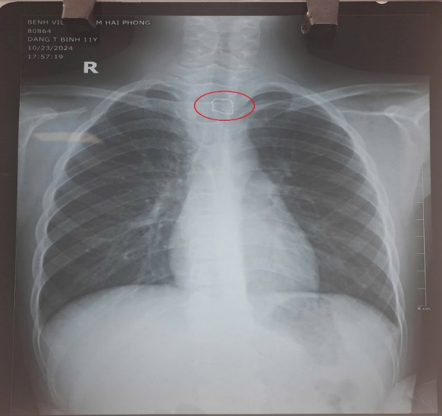

| Hình ảnh dị vật là hàm duy trì đã được bác sĩ xử trí kịp thời. Ảnh BVCC |

Qua kết quả cận lâm sàng, các bác sĩ phát hiện một vật cản quang, được xác định là dây kim loại nằm tại vị trí thực quản đoạn cổ. Ngay sau đó, bệnh nhi được gây mê và nội soi khẩn cấp, gắp chiếc hàm duy trì kích thước gần 3 cm ra khỏi đoạn 1/3 trên của thực quản một cách an toàn. Sau quá trình nội soi, sức khỏe của cháu bé đã ổn định.